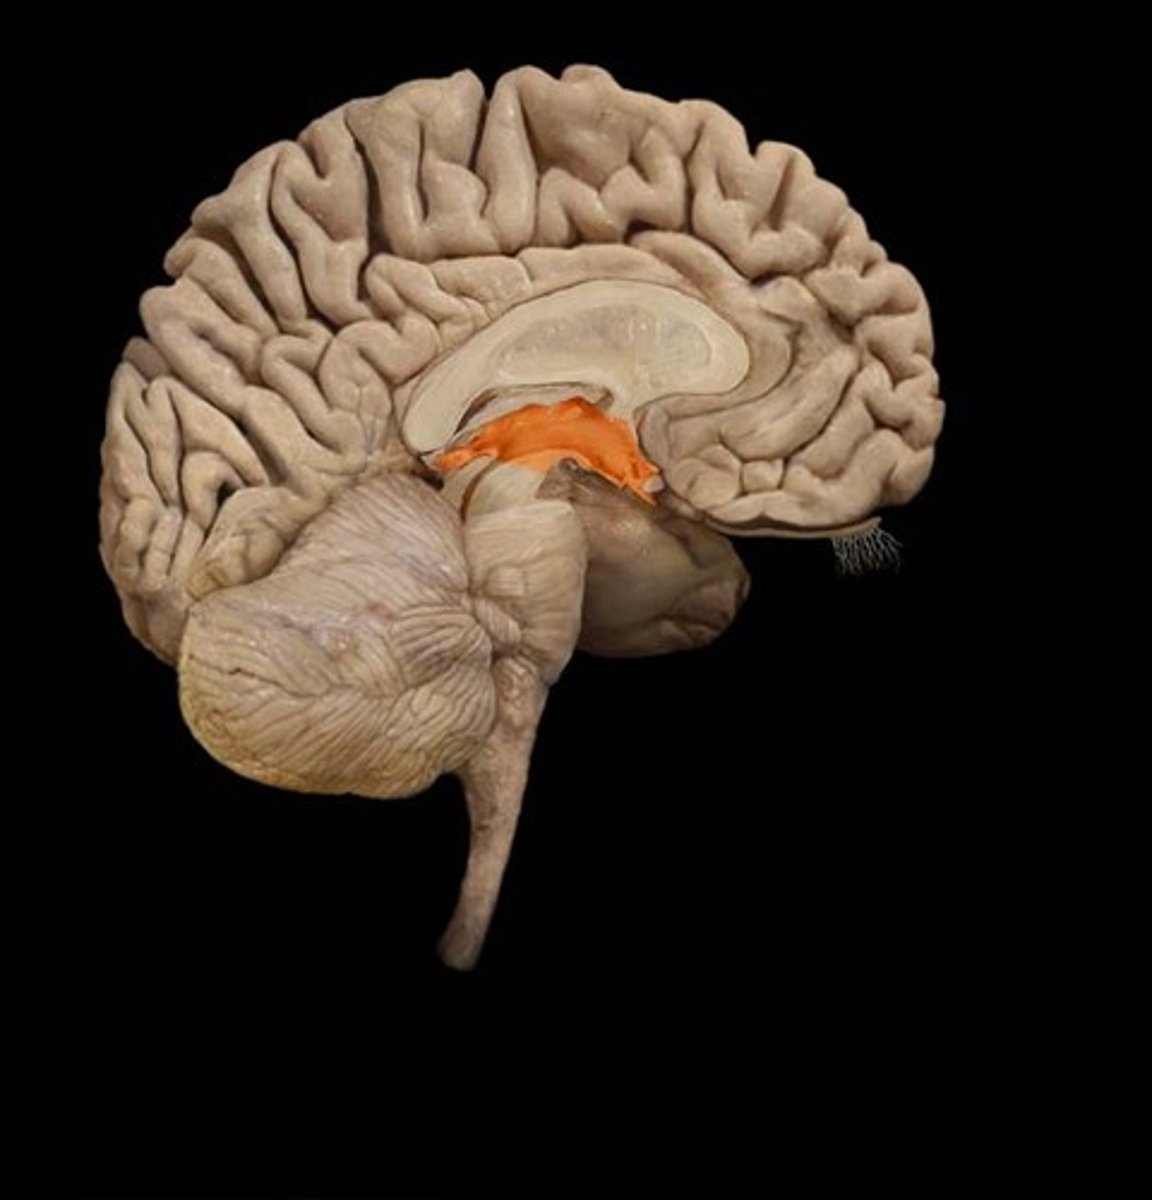

Diencephalon

thalamus, hypothalamus, epithalamus

thalamus

the brain's sensory switchboard, located on top of the brainstem; it directs messages to the sensory receiving areas in the cortex and transmits replies to the cerebellum and medulla

hypothalamus

A neural structure lying below the thalamus; it directs several maintenance activities (eating, drinking, body temperature), helps govern the endocrine system via the pituitary gland, and is linked to emotion and reward.

epithalamus

Contains pineal body. Involved in olfactory senses and sleep/wake cycle- melatonin